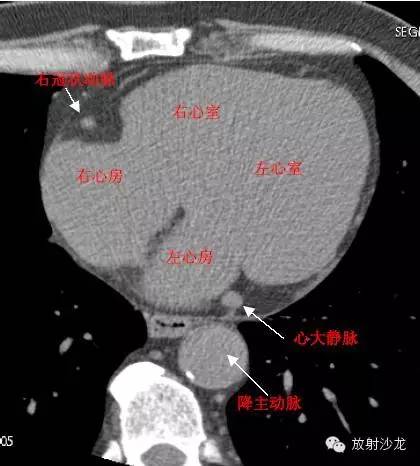

LA -Left Atrium左心房

RA -Right Atrium右心房

LV -Left Ventricle左心室

RV -Right Ventricle右心室

D. Aorta-Descending Aorta降主动脉

GCV–Great Cardiac Vein心大静脉